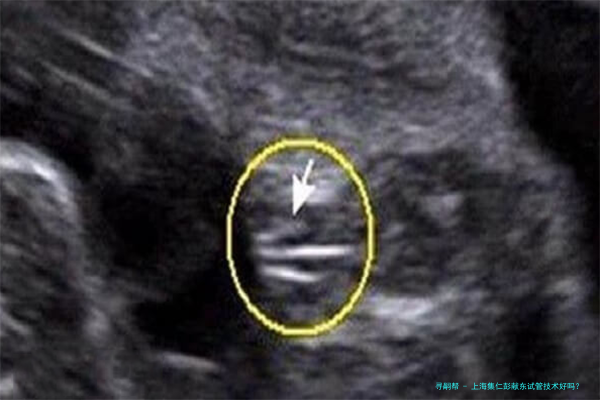

试管婴儿技术是一种人类辅助生殖技术,主要适合于因各种缘故导致的试管婴儿助孕夫妇。这个技术通过将卵子和精子在体外受精后,培育成初期胚胎,又将胚胎移植到本人体内内不断发育,一直到分娩。上海集仁遗传与不育诊疗中心的试管婴儿技术涵盖了多个方向,囊括但不仅限于:

PGD/PGS(胚胎植入前基因诊断/筛选):运用于筛选出正常的胚胎进行移植,降低遗传性疾病传达的风险。